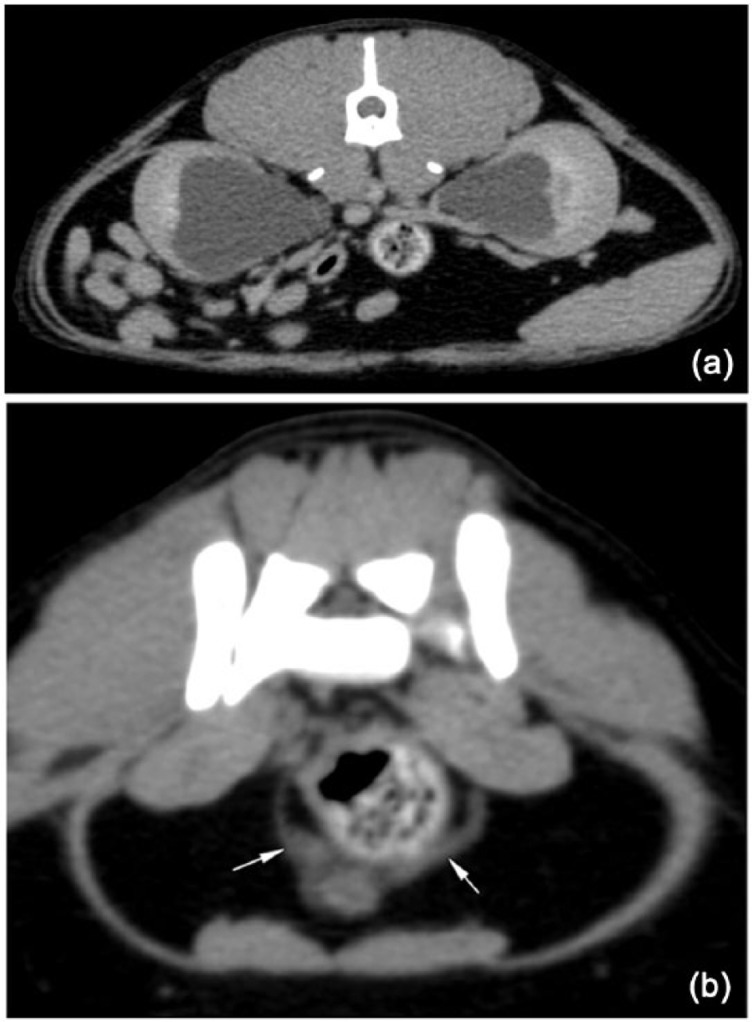

This examination identified moderate bilateral hydronephrosis and diffuse mild-to-moderate hydroureter (Table 3; Figure 1a,b). On the postcontrast images there was a normal parenchymal phase; however, the excretory phase was delayed.

Figure 1.

(a) Transverse computed tomographic (CT) images showing bilateral hydronephrosis in a cat with urinary tract obstruction due to bladder torsion. (b) Transverse CT images showing bilateral hydroureter (arrows) in a cat with urinary tract obstruction due to bladder torsion